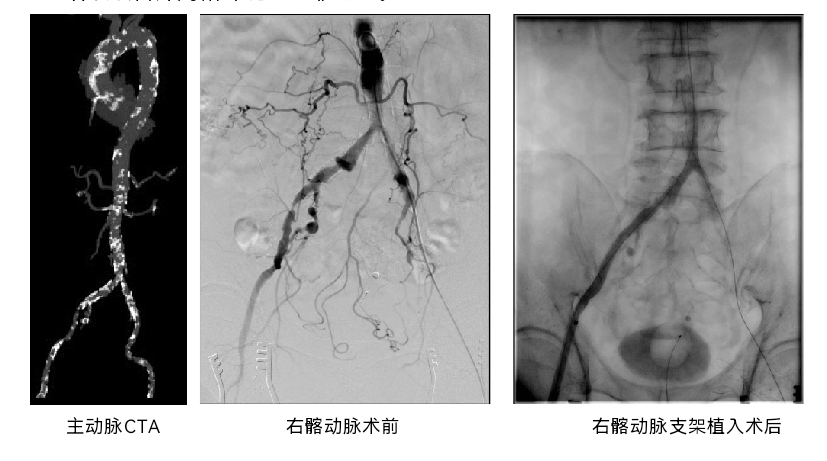

经检查,王老伯的冠状动脉血管已经发生了再次闭塞,更为严重的是他被发现同时合并了严重的主动脉瓣狭窄,主动脉瓣口有效开放面积仅0.9cm²,仅相当于正常水平的约1/3,心脏的收缩功能也已经出现了明显的恶化降低。进一步检查后,又发现他双侧髂动脉重度狭窄,其中右侧濒临完全闭塞状态。叠加高龄、已接受过开胸搭桥手术、缺少供体血管等因素,再次开胸手术治疗已“无路可走”,常规的介入治疗路径也存在巨大挑战。

先由心内科团队完成右冠脉慢性完全闭塞(CTO)病变介入治疗,植入支架,改善冠脉供血,为后续治疗提供保障;再用经导管方式置换主动脉瓣(TAVR),由心外科与血管外科通过局部切开后穿刺股动脉,球囊扩张狭窄的髂动脉后建立了TAVR入路,心内科团队完成植入26mm球囊扩张式瓣膜;最后由血管外科团队完成髂动脉支架植入,同台解决其髂动脉狭窄问题。